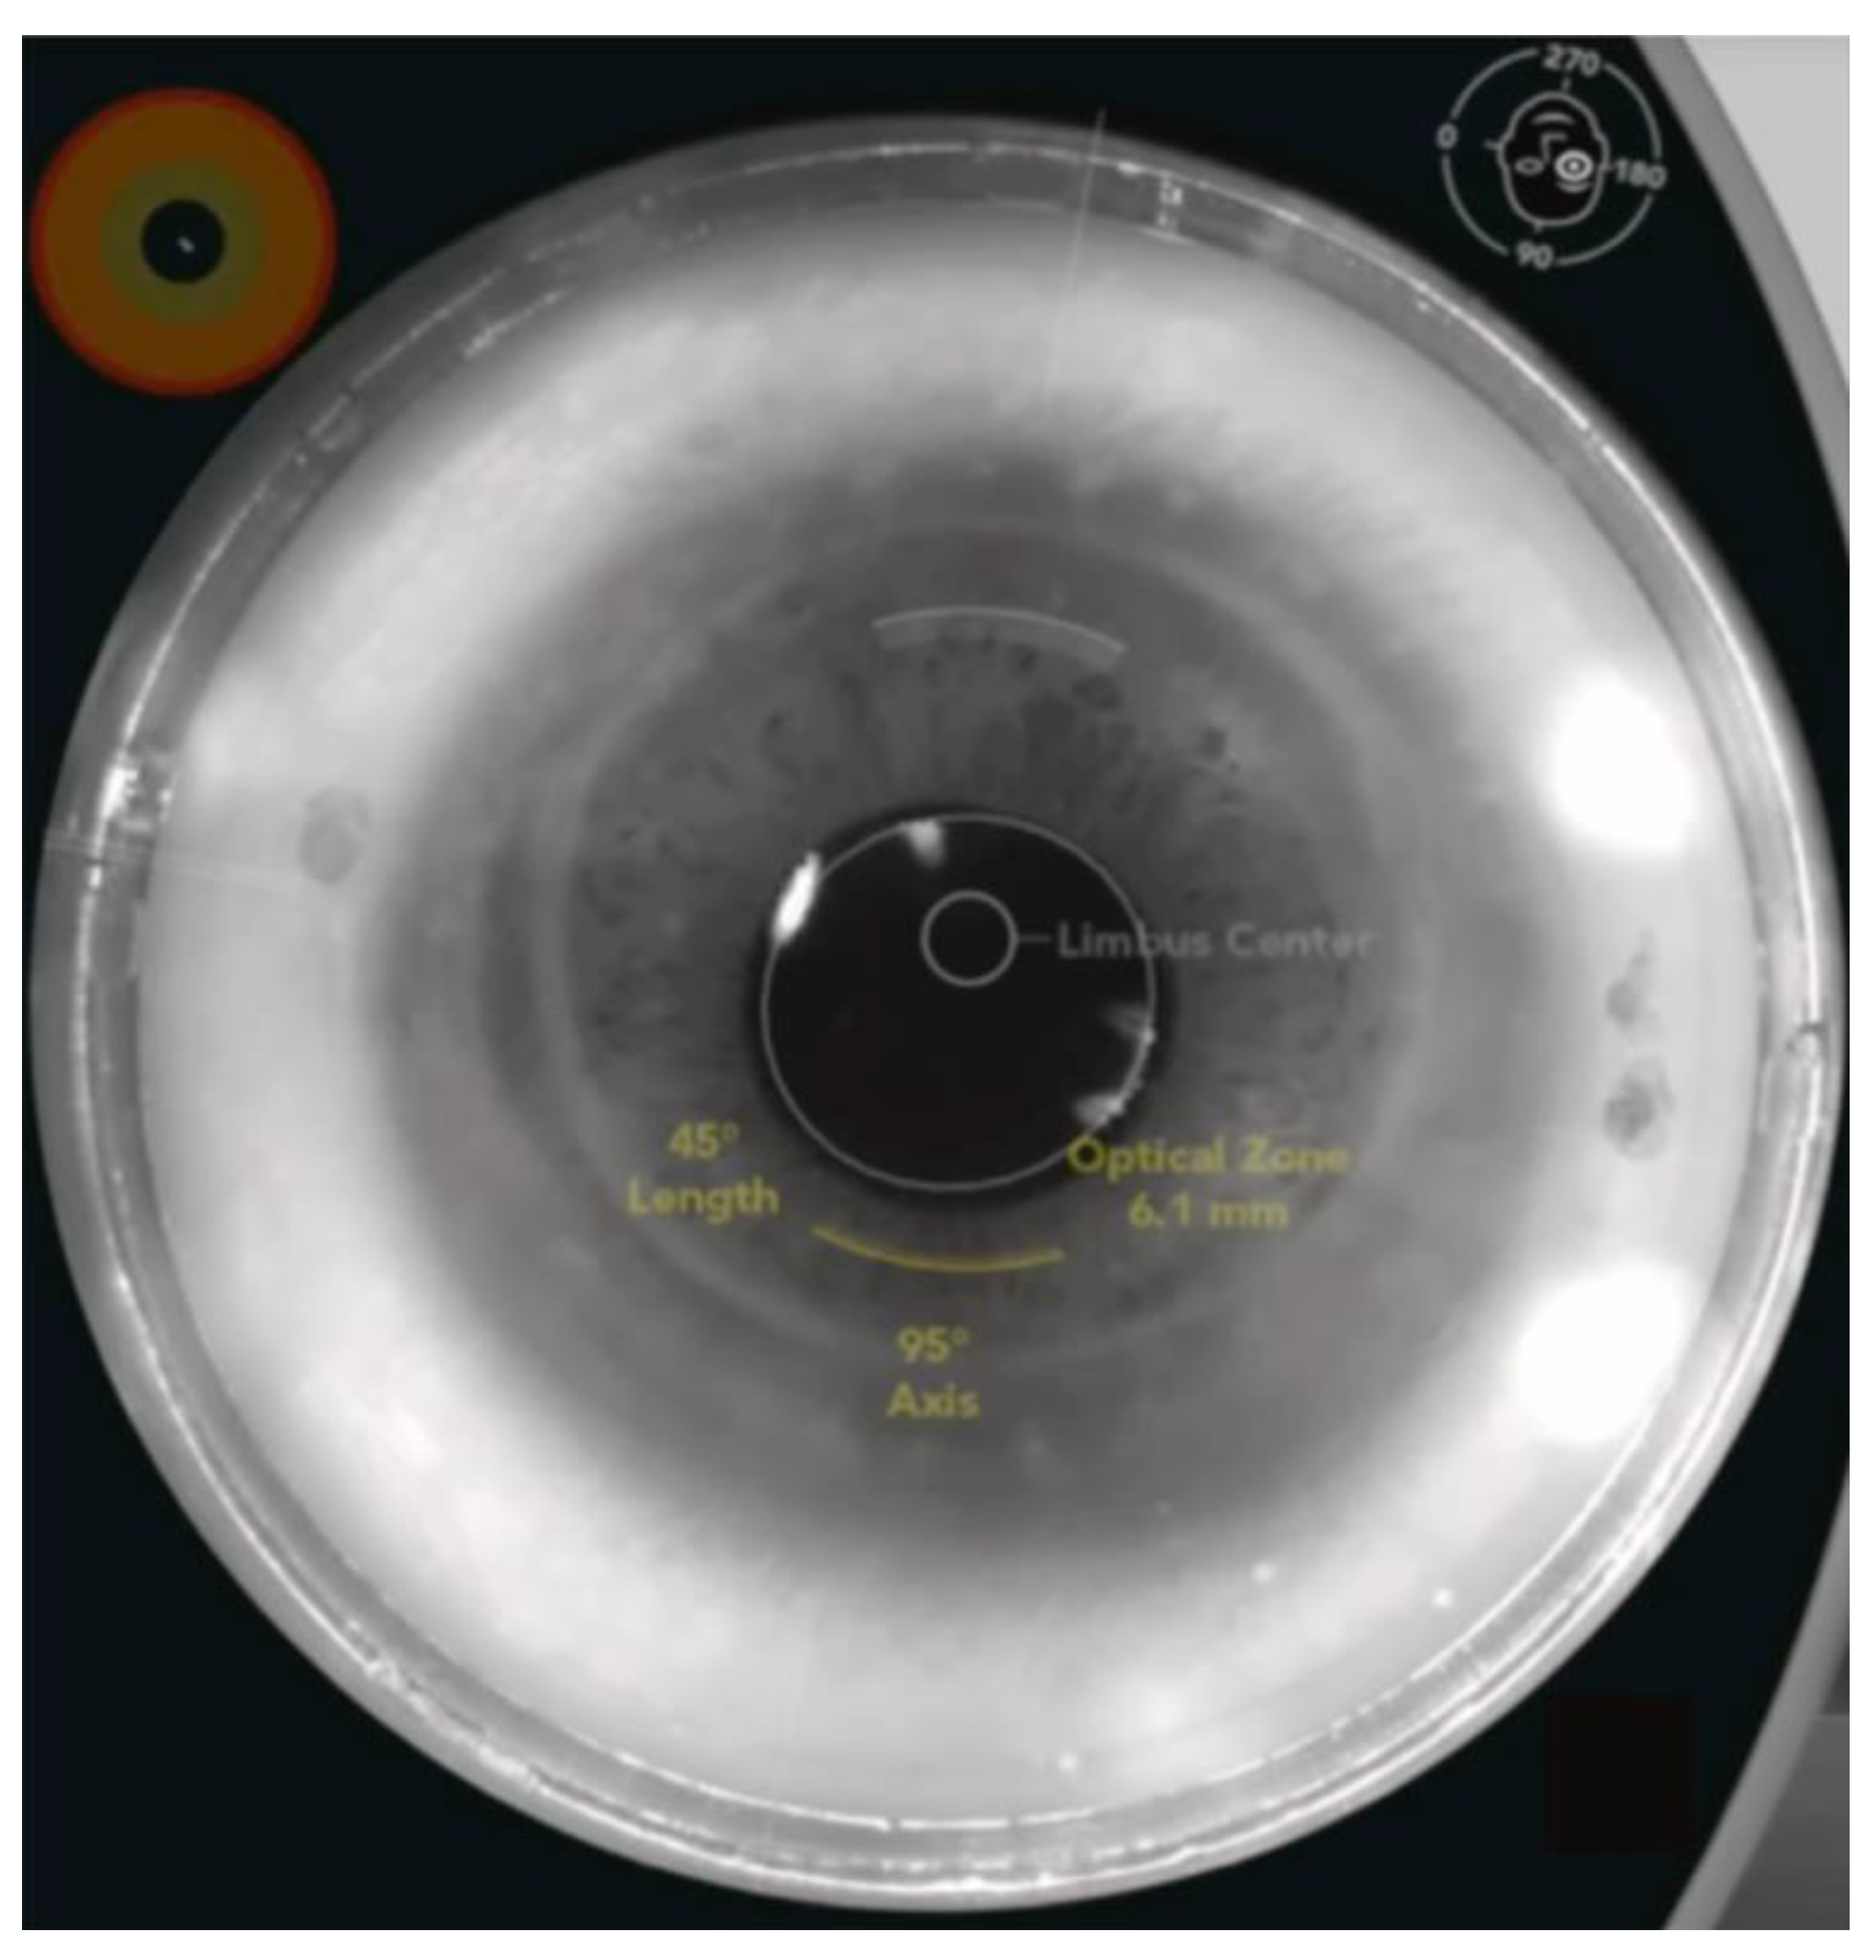

- Schwarzenbacher, L.; Schartmüller, D.; Roeggla, V.; Meyer, E.; Leydolt, C.; Menapace, R. One-Year Results of Arcuate Keratotomy in Patients with Low to Moderate Corneal Astigmatism Using a Low-Pulse-Energy Femtosecond Laser. Am. J. Ophthalmol. 2021, 224, 53–65. [Google Scholar] [CrossRef]